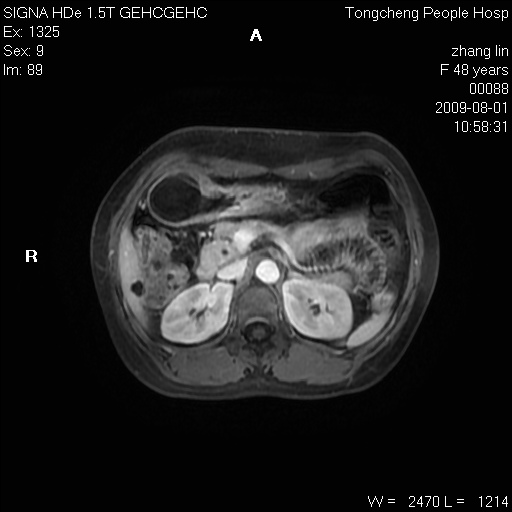

女,48岁。健康体检,彩超发现右肾占位性病变。平素健康。

临床诊断:右肾占位性病变,性质待定(囊肿?肿瘤?)。

上中腹部mr平扫+增强扫描,图像如下:

右肾上极见一类圆形病灶,t1wi呈等信号t2wi呈等高混杂信号,三期增强无强化,边界清---考虑囊肿出血。

同反相位均表现为等信号,病变无强化,考虑含蛋白的囊肿可能,弥散加权相或许有些帮助,

慢性胆囊炎